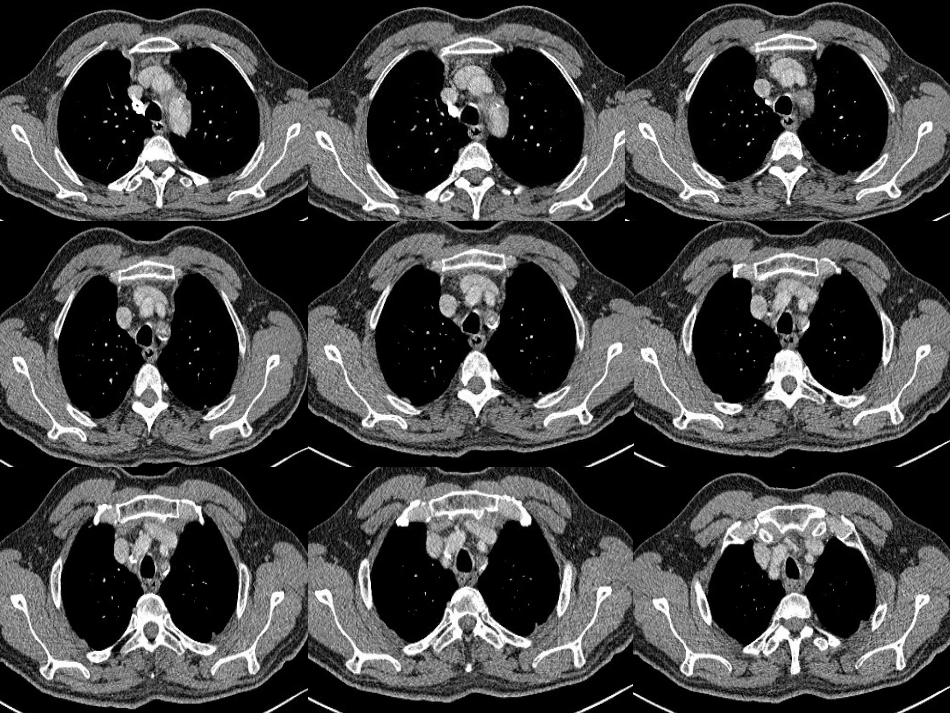

Bonegroup2012.6.7HistoryMale,62yearsoldAtransientsyncopeSphygmus:72times/min,left--weakBloodpressure:rightarm—110/70mmHgleftarm—70/50mmHgPossiblediagnosis?Why?FinaldiagnosisImageimpression:Subclavianarterywallcalcification,stenosis;thrombosiscannotbeexcludedClinicaldiagnosis:SubclavianStealSyndrome(SSS)SubclavianStealSyndromeDefinition:Subclavianstealsyndromeistheproximalsubclavianarteryorinnominatearteryobstruction(causedbyavarietyofreasons),Subclavianarterydistalintraluminalpressuredecreased,ipsilateralbloodpressurebelowthevertebral–basilararterialpressure---syphonage,soresultinSSSClinicalmanifestationsupperlimbsymptom:Somepatientscomplainedofweakness,numbnessandpainwhentheupperlimbsexerciseVertebrobasilarinsuficiencysymptom:Syncope,dizziness,vertigo,standinginstabilityandoccipitalpainisthemostcommoncomplaintcarotidarteryinsufficiencysymptom:rarely,butcanoccurinthepatientofinnominatearteryobstructionPhysicalfindingsIpsilateralradialarterypulseweakenedordisappeared,bilateralpulsenonsynchronization(delay0.03~0.06s)Pressuredifferential(PD)>20mmHg(contralateral>Ipsilateral)(Only16%ofthepatientswithaPD20mmHgdidnothaveSSS.ThisresultsuggeststhatarmBPdifferential20mmHgishighlycorrelatedwiththepresenceofSSS)PhysicalfindingsTheipsilateralsupraclavicularfossavascularbruit(systolic)Javidtest:positive(aftertheoppressionofthecommoncarotidartery,radialarterypulseweakened)PathogenyArteriosclerosis(mostcommon)Congenitalmalformations(aorticstenosis,subclavianarterydistalatresia)Takayasuarteritis(tuberculosis,syphiliticaortitis)TumorcompressionRadiotherapySSSbloodpathway(一)VA-VAcontralateralvertebralartery↓vertebrobasilararteryconfluence↓ipsilateralvertebralartery↓ipsilateralsubclavianarterydistalSSSbloodpathway(二)BA-VAbasilarartery↓ipsilateralvertebralartery↓ipsilateralsubclavianarterydistalSSSbloodpathway(三)PCA-BA-VAposteriorcerebralartery↓basilarartery↓ipsilateralvertebralartery↓ipsilateralsubclavianarterydistalSSSbloodpathway(四)OA-VAexternalcarotidarterybranchoccipitalartery↓occipitalarteryandvertebralarteryanastomoticbranch↓vertebralartery↓subclavianarterydistalDiagnosticmethods(一)Dopplerultrasoundexamination※Observethebloodflow※VertebralarteryappearingreversespectrumisthetypicalperformanceofSSSA,Normalflowinapatientwithoutsubclavianstealsyndrome(SSS).Ithasalowwavepatternresistancewithcephaladflowthroughoutthecardiaccycle.B,FlowvelocitywaveformintheleftvertebralarteryindicatingapartialSSS.Theflowduringsystoleandthebeginningofdiastoleisreversed.Therewasa25mmHgPD.C,CompletestealinapatientwitharmbloodPDof60mmHg.Theflowinthevertebralarteryisreversedthroughoutthecardiaccycle.TheseveritycanbegradedbasedonthevertebralDopplerspectralpatterns:I:antegradeflowwithdiminishedpeaksystolicvelocityII:alternatingflow—antegradeflowinthediastolicphaseandretrogradeflowinthesystolicphaseIII:completelyretrogradeflowDiagnosticmethods(二)DigitalSubtractionAngiography—DSA※DSA---thegoldstandardstodiagnoseSSSthedegreeofSubclavianarterystenosisthelocationofsubclavinaarterytheprogressoftherefluxbloodflow(thecontralateralvertebralartery→theipsilateralvertebralartery→theipsilateralsubclavianarterydistal)※limitionexpensive,invasive,difficulttorepeatsensitivetocompletedstenosis,bu...